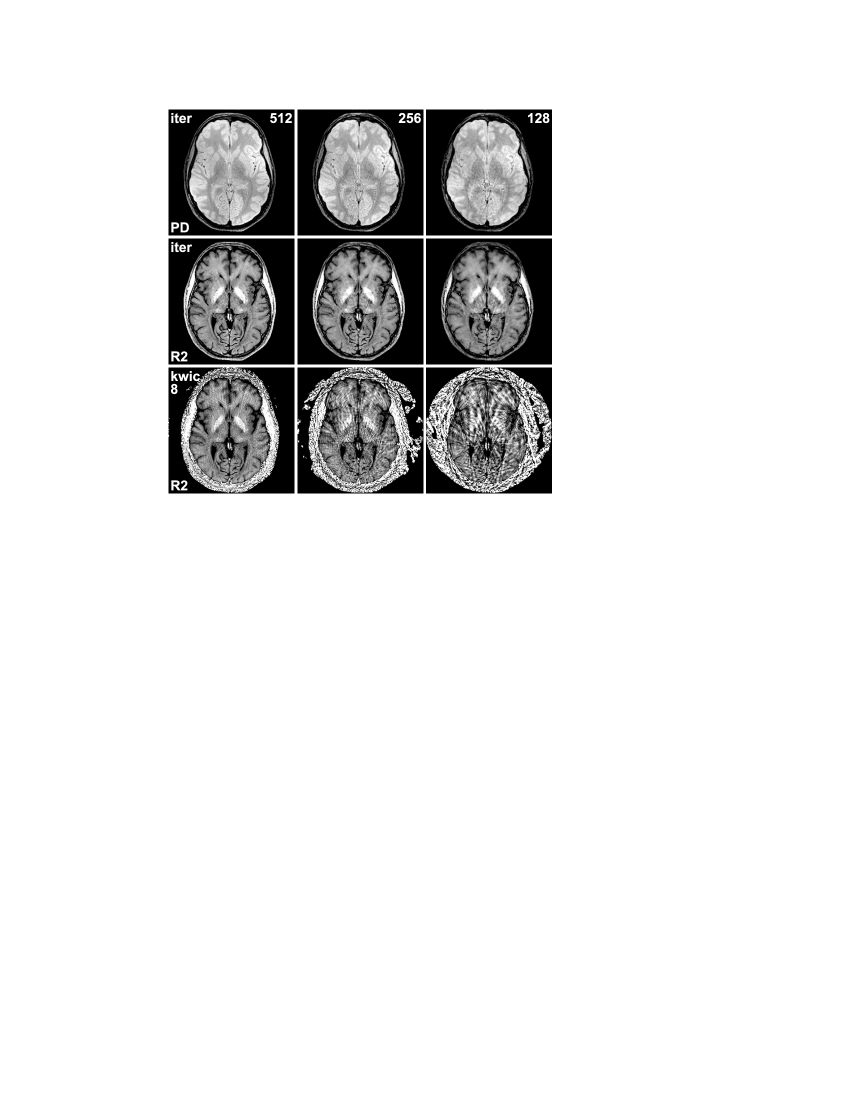

Finally, Fig. 4 shows iterative reconstructions of the human brain from radial data with different degrees of undersampling, ranging from a total of 512 spokes (32 repetitions) to only 128 spokes (8 repetitions). As expected, the data reduction is accompanied by some loss of image quality, but even for 128 spokes the iterative approach still offers a relatively good separation of proton density and relaxivity. For comparison, relaxivity maps obtained by the KWIC approach are shown in the bottom row, and it can be seen that the image quality breaks down for higher degrees of undersampling.